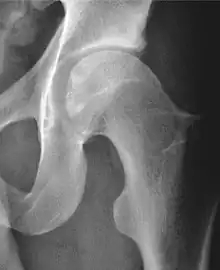

Plain radiography allows us to categorize the hip as normal or dysplastic or with impingement signs (pincer, cam, or a combination of both). Besides these, pathologic processes like osteoarthritis, inflammatory diseases, infection, or tumors can also be identified (Figure 1).[1]

Figure 1.

Radiography in normal hip

X-ray in pincer impingement type of hip dysplasia

X-ray of cam

Hip in osteoarthritis

Septic arthritis